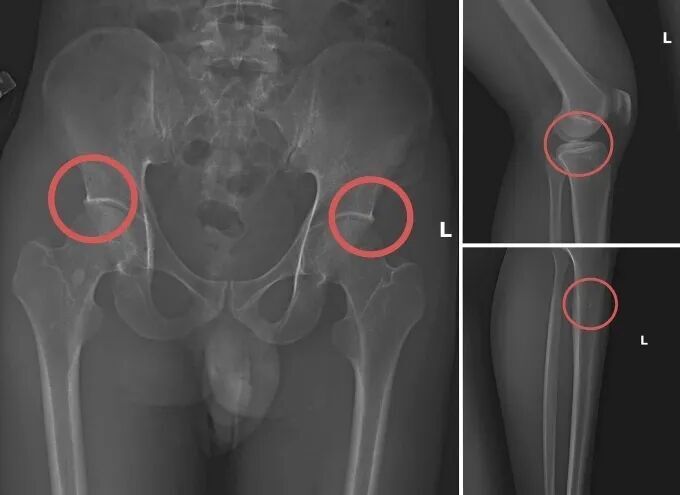

案中主谋是原锦溪县医疗中心(Trung tâm Y tế huyện Cẩm Khê)的卫生系统干部谢明洲(Tạ Minh Châu)。他竟利用自身的专业医学知识,策划并实施了一套系统性的骗保流程:先是诱使他人购买高额人寿保险,随后亲自为他们注射麻醉剂,在受害者意识不清的情况下,使用钉锤等工具,冷酷地凿断他们的骨骼,人为制造出与真实事故几乎无法区分的骨折痕迹。

他还知道哪些部位的骨折能获得最高额的赔偿,从而在作案时能够"精准下手",刻意在赔付率高的骨骼位置制造伤害。这种利用专业知识进行的犯罪,极具隐蔽性和欺骗性,使得保险公司在常规审核中难以察觉异常,误以为这些是真实的意外伤害事故。

这是该团伙进行麻醉和骨科手术的现场